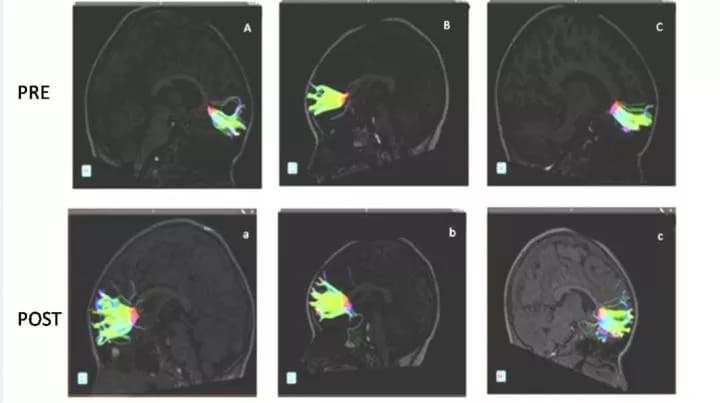

The study participants underwent pre- and post-musical-training evaluation with diffusion tensor imaging (DTI) of the brain. DTI is an advanced MRI technique, which identifies microstructural changes in the brain's white matter.

The brain's white matter is composed of millions of nerve fibers called axons that act like communication cables connecting various regions of the brain. Diffusion tensor imaging produces a measurement, called fractional anisotropy (FA), of the movement of extracellular water molecules along axons. In healthy white matter, the direction of extracellular water molecules is fairly uniform and measures high in fractional anisotropy. When water movement is more random, FA values decrease, suggesting abnormalities.

After the children in the study completed nine months of musical instruction using Boomwhackers -- percussion tubes cut to the exact length to create pitches in a diatonic scale, DTI results showed an increase in FA and axon fiber length in different areas of the brain, most notably in the minor forceps.